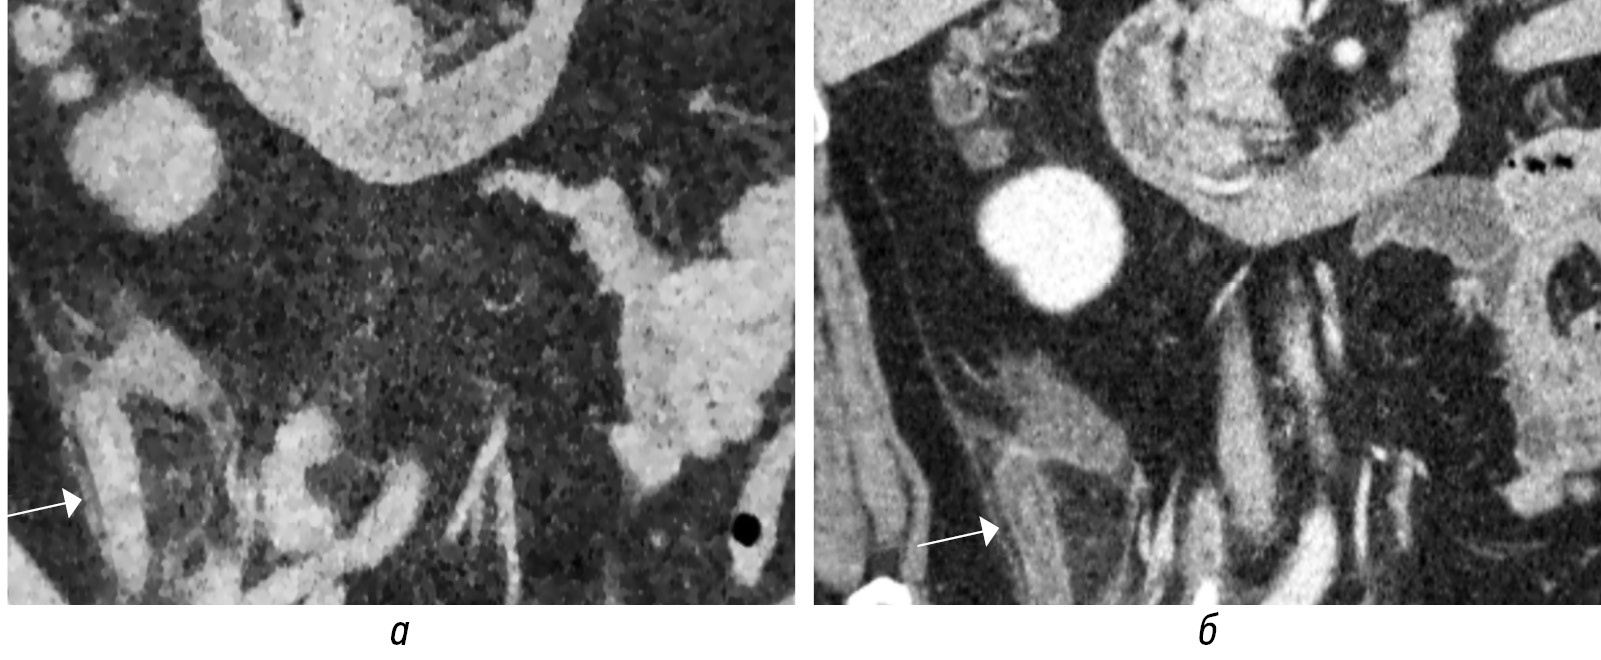

Однако в позднем отчете этих же авторов критерий «любой из 10 признаков» предлагается использовать только при наличии прямых признаков КТ ОА [20]. Применение критерия любого из 10 признаков к пациентам независимо от оценки вероятности ОА привело к снижению специфичности. Например, такие предикторы, как внутрипросветный газ (рис. 5, а, б) или внутрипросветный аппендиколит могут наблюдаться и в нормальном аппендиксе [20]. Известно, что феколиты могут быть обнаружены в нормальном аппендиксе без визуализационных и гистопатологических признаков воспаления [2, 14] (рис. 12, а, б). Другие авторы считают, что аппендиколиты связаны с более высокой частотой перфораций, и предполагают увеличение частоты неудач консервативной антибиотикотерапии неосложненного ОА из-за того, что аппендиколит служит очагом продолжающейся или рецидивирующей инфекции [2, 24]. По данным исследований, у взрослых с подтвержденным ОА аппендиколит был обнаружен в 30–40 % случаев. [2, 24]. Ranieri D.M. et al. при КТ обнаружили аппендиколиты у 38,7 % (96/248) пациентов с ОА; у 4,4 % (11/248) аппендиколиты отсутствовали [24].

Рис. 12. КТ-изображения во фронтальной (а) и аксиальной (б) плоскостях в артериальную фазу. При КТ-ангиографии случайно выявлен аппендиколит в устье аппендикулярного отростка (стрелки) с увеличением диаметра аппендикса до 10 мм, без клинико-лабораторных данных за острое воспаление. Купол слепой кишки (а, пунктирная стрелка)

Fig. 12. CT images in the frontal (а) and axial (б) planes in the arterial phase. CT angiography accidentally revealed appendicolitis at the mouth of the appendicular process (arrows) with an increase in the diameter of the appendix to 10mm, without clinical and laboratory data for acute inflammation. The dome of the cecum (а, dotted arrow)

Просвет аппендикса может расширяться за счет неоднородного внутреннего содержимого без наличия (рис. 6, а, г) или с присутствием (рис. 6, б, в, д, е) аппендиколита. Другие косвенные признаки ОА: отек периаппендикулярной жировой клетчатки (рис. 7, а, б; 8, а, б); утолщение за счет отека прилежащей стенки кишки (рис. 9, а–г); расширение просвета кишки за счет газа иди жидкости с ослабленной перистальтикой; периаппендикулярное жидкостное скопление или абсцесс (рис. 10, а, б); лимфоаденопатия (рис. 11, а); абдоминальный выпот (рис. 11, г) [3, 16, 18].